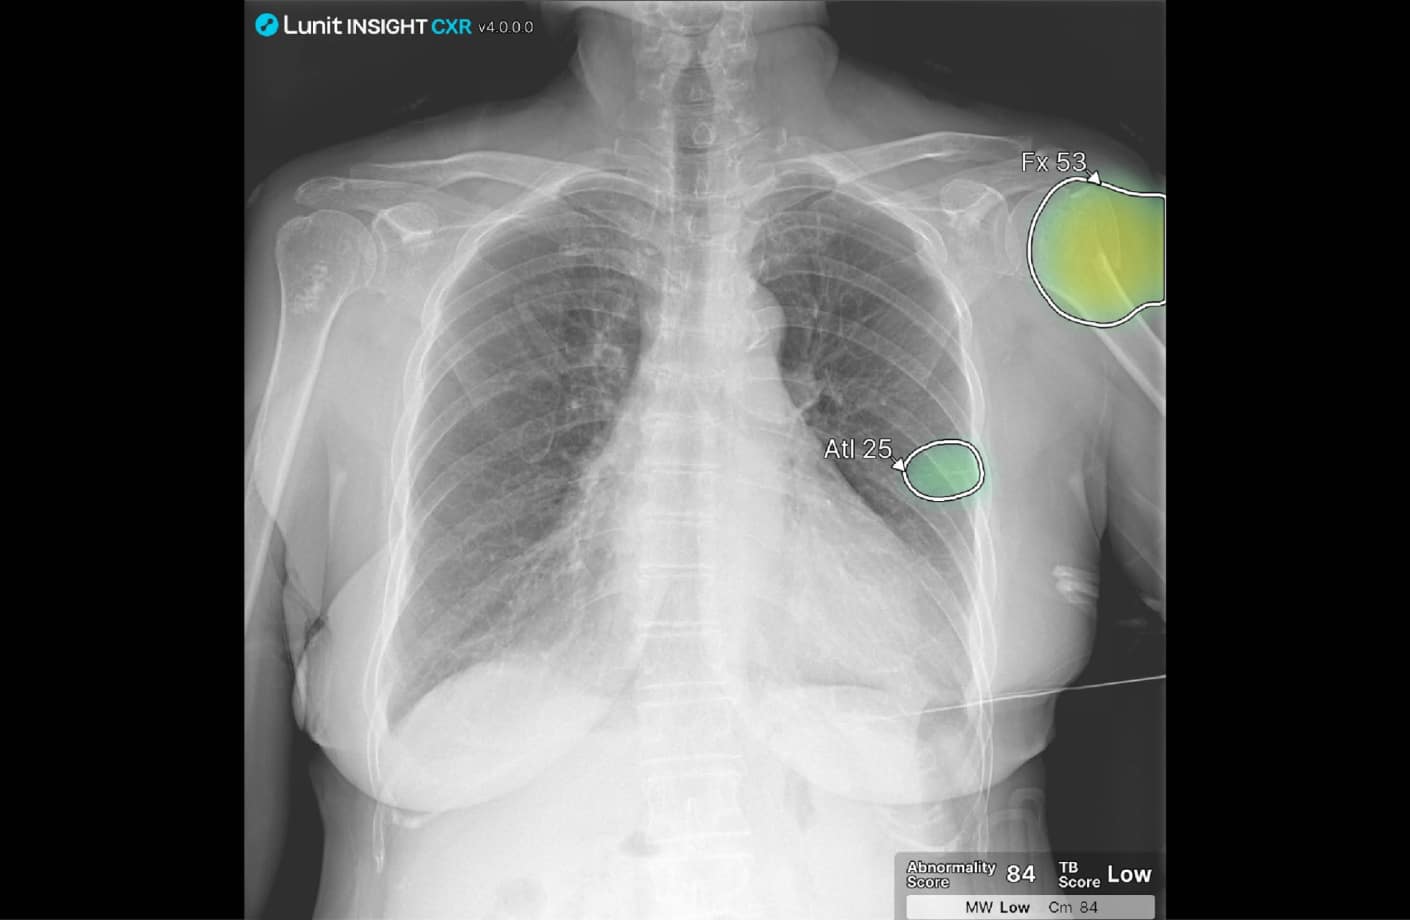

À l’écran, le rendu est très parlant : les zones suspectes sont directement mises en évidence sur la radio du thorax, avec des scores clairs qui rendent les suggestions de l’IA faciles à comprendre au quotidien. Cela permet aux radiologues, aux prescripteurs et aux patients de profiter d’une IA pratique et transparente, loin de l’image de la « boîte noire ».

CXR Insight est un logiciel d’intelligence artificielle qui analyse automatiquement les radiographies thoraciques pour détecter les principales anomalies. Il affiche des cartes de chaleur et des scores pour aider à interpréter les images plus rapidement et plus sereinement.